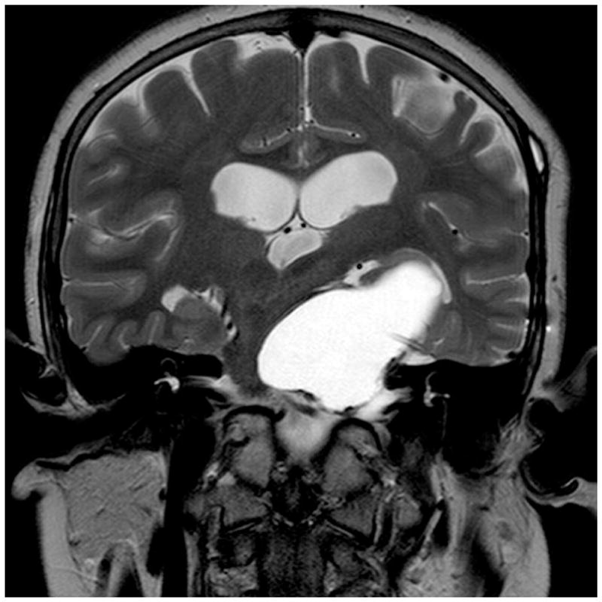

CT和MRI都可用于診斷。腦部CT通常顯示囊性腫塊伴鈣化。腦積水在放射學上并不罕見。MRI精確顯示了腫瘤塊,其總體形態(tài)及其與血管和主要顱內(nèi)動脈的關(guān)系。對比增強通??擅鞔_囊壁,并可以觀察到腫瘤的實體部分。

圖為小俊手術(shù)前后對比,腫瘤順利切除